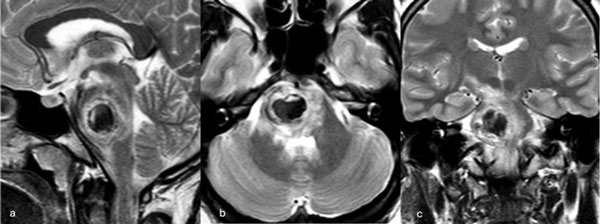

Una paciente femenina de 28 años, sin antecedentes de sangrado previo, debutó con cefalea, náuseas y vómitos, asociado a diplopía secundaria a una parálisis del VI par derecho. La RM de encéfalo evidenció una malformación cavernomatosa centrada en puente y el pedúnculo cerebeloso medio derecho (Figura 3). Un mes después del sangrado, se realizó una exéresis de la lesión mediante un abordaje retrosigmoideo ampliado a través del pedúnculo cerebeloso medio (Figura 4), logrando una exéresis completa (Figura 5). Tras el procedimiento, la paciente evolucionó con hemihipoestesia del hemicuerpo izquierdo, sin otros síntomas agregados.

Figura 3. RM preoperatoria de encéfalo. Se evidencia una lesión única intraaxial centrada en puente y pedúnculo cerebeloso derecho, sugerente de un cavernoma roto. A, B y C) Imágenes ponderadas en T2 en cortes sagital, axial y coronal, respectivamente, donde se observa un importante hiperintensidad perilesional, sugerente de edema.